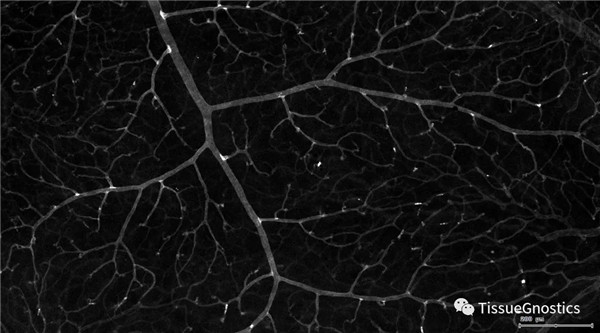

單通道灰階圖(↑:FITC,↓:Texa Red)

血管識(shí)別:根據(jù)Texa Red通道進(jìn)行識(shí)別,并去除面積小的及非同一焦面的血管,僅對(duì)確定的清晰的同一焦面的大血管進(jìn)行面積統(tǒng)計(jì)。

血管與小膠質(zhì)細(xì)胞的距離

血管與小膠質(zhì)細(xì)胞的距離0-0.1μm(紅色框線標(biāo)記)

血管與小膠質(zhì)細(xì)胞的距離0.1-1μm(粉色標(biāo)記)

血管與小膠質(zhì)細(xì)胞的距離1-3μm(粉色標(biāo)記)